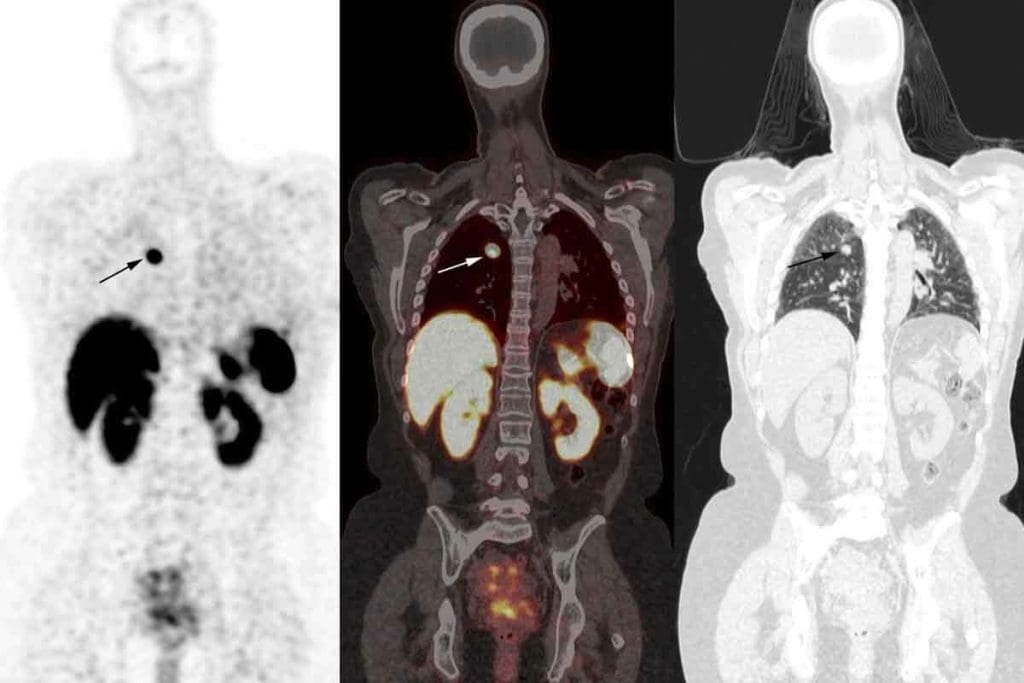

Cancer Detection Through Bone Scan Images

Bone scintigraphy, using technetium 99m, is a top-notch method for spotting bone metastases and primary bone cancers. It’s a key tool in oncology, helping doctors find and track cancer in bones.

Metastatic Disease Patterns

Metastatic bone disease is a big problem for cancers like breast, prostate, and lung. Bone scans are great at finding these lesions, showing patterns like multiple spots all over the skeleton.

A study on breast cancer patients showed bone scans found metastatic bone disease in about 30% of cases. This highlights how important bone scans are in cancer care.

Cancer Bone Scan: Normal vs. Abnormal Findings

Telling normal from abnormal on a cancer bone scan is vital for correct diagnosis and care. Normal scans show even uptake, with some areas active due to bone metabolism.

Abnormal scans, though, show “hot spots” or areas with less uptake, pointing to diseases like cancer. Below is a table showing the main differences between normal and abnormal bone scan findings for cancer detection.